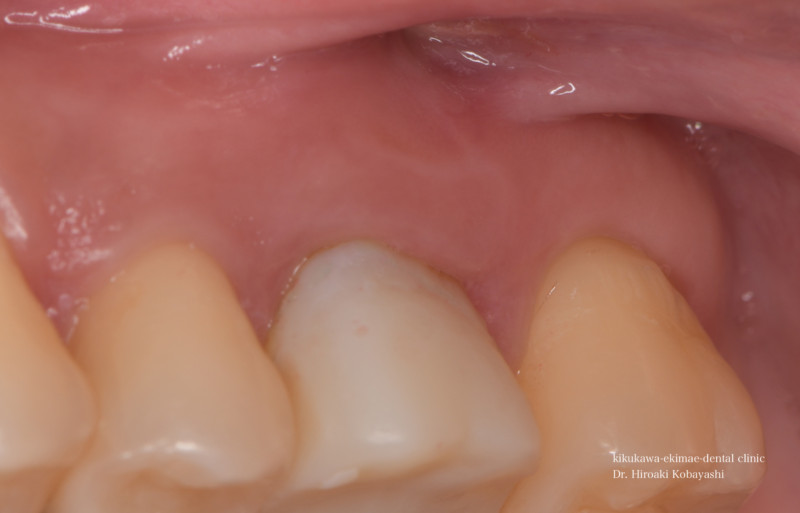

歯茎からオデキが出来たと来院されました。 CT撮影を行いますと、根の感染が見られました。感染の長期の放置により骨が溶けており、歯の保存が難しそうな状況でした。痛みもなく、特に生活に支障はありませんが、刻一刻と早期に歯を失う方向に進んでいます。おそらく、数年このままですと痛みもなくある日、ぐらぐらし、抜け落ちていたでしょう お話し合いの上、精密根管治療にて歯の保存を希望されましたので、治療を開始しました。   時間をかけ、顕微鏡を使用し感染の除去を行なっていきます。過去に根の処置を行なった時に入れたであろう薬剤や膿や出血が出てきます。 2時間程度のアポイントを3回お取りし、精密根管治療が完了しました。 オデキはなくなり、無事歯を残す事が出来ました。   CTにて経過を見ますと骨の再生が起きています 約6ヶ月〜程度かけて骨の再生が起こります。 リスク 極端に硬いものを噛むとかける可能性があります。 各種治療費はこちらから